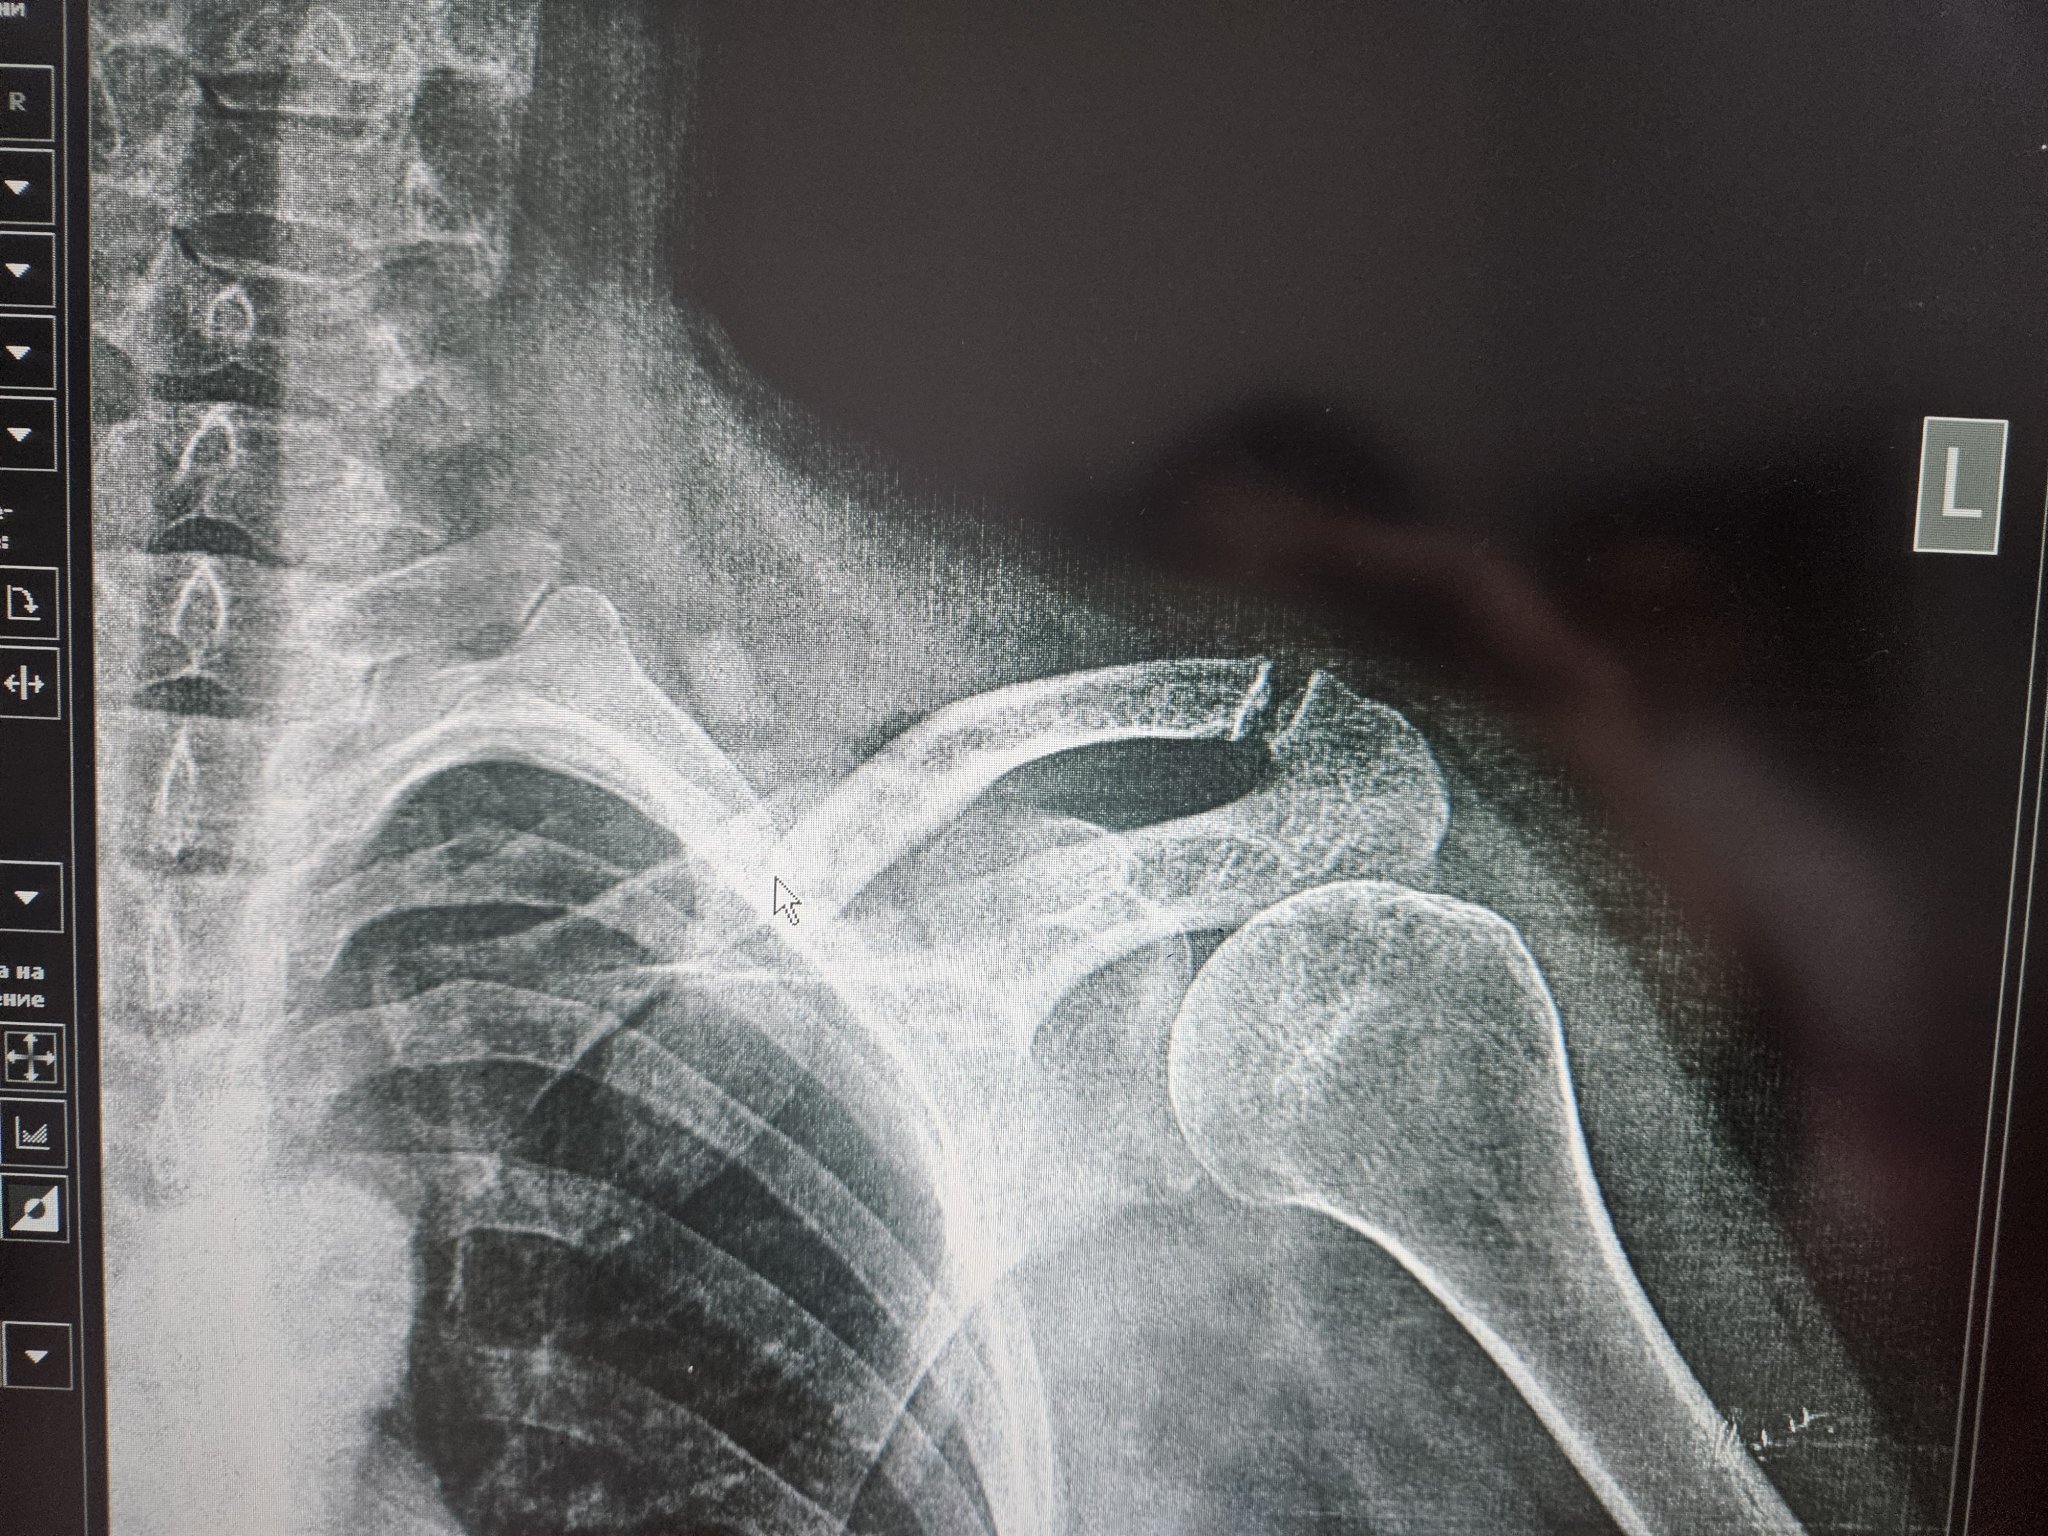

Какво е препоръчителното лечение за частична руптура на сухожилието на m.supraspinatus при раменна травма?

Направете рентгенова снимка на ходилото фас и профил (ако кривата кост е на ходилото).